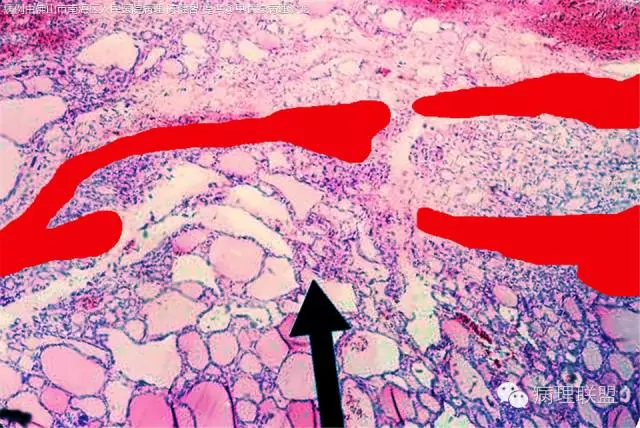

请教各位同行专家一个病例。F/42,右甲状腺发现2个结节,其中一个如下图,另一个是完全钙化结节。术前外院做的超声,来我们院做的CT,报告边界清楚。(病例由佛山市南海区人民医院病理 陈健智 提供,致谢!)